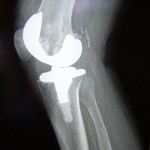

In that post I mentioned that anybody who has a joint replacement is supposed to get antibiotics prescribed to them before certain dental procedures. The reason for this is that there are millions of bacteria in our mouth that may enter our bloodstream during certain dental procedures. When an artifical joint gets infected, it normally is considered a failure.

Since antibiotics are very cheap and they can help prevent the infection of an artificial joint, it seems like a no-brainer to give antibiotics to patients before invasive dental procedures so that the catastrophic loss of an artificial joint can be avoided.